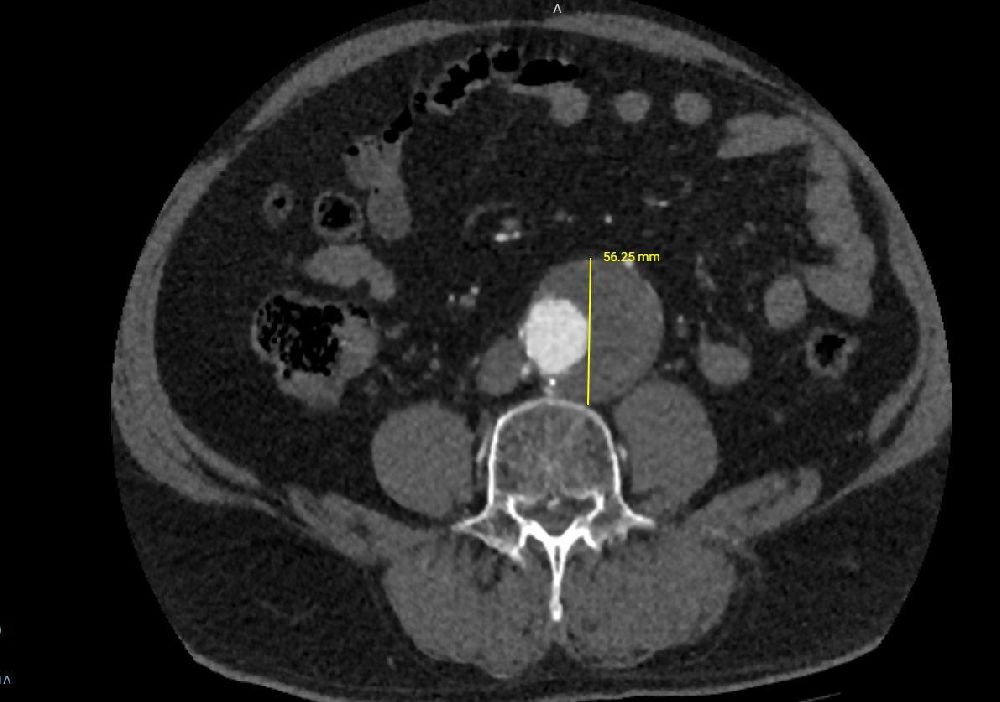

Karın aort anevrizması, vücudun en büyük atardamarı olan aortun karın bölgesindeki genişlemesiyle ortaya çıkan, ciddi ve hayati risk taşıyan bir hastalıktır. Kontrol altına alınmadığında damarın yırtılmasına (rüptür) neden olabilen bu durum, erken müdahale gerektiren kritik bir sağlık sorunudur. 68 yaşındaki hastanın yapılan tetkiklerinde, aort damarında 56 mm’ye ulaşan bir genişleme tespit edildi ve bu yüksek riskli tablo karşısında EVAR prosedürü uygulanmasına karar verildi.

Operasyon, kasık bölgesinden yapılan küçük kesiler aracılığıyla minimal invaziv şekilde gerçekleştirildi. Genişleyen damar bölgesine özel bir greft kaplı stent yerleştirilerek anevrizmanın bulunduğu bölge izole edildi ve damarın normal akışı sağlandı. Bu yöntem sayesinde hastanın iyileşme süresi de açık cerrahiye göre daha hızlı ve konforlu hale geldi.